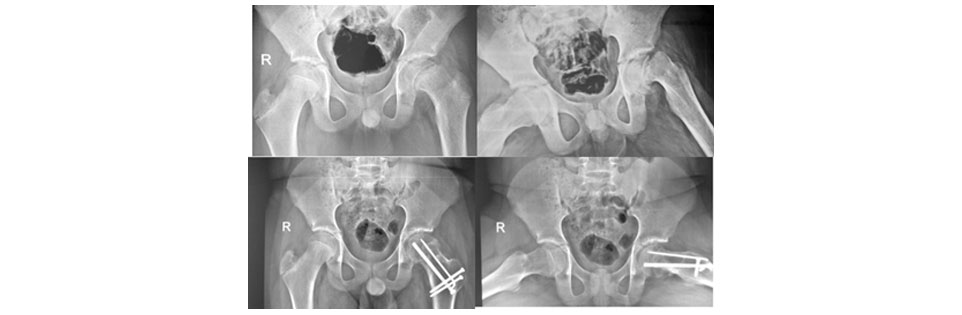

Figure 2: Showing pre-operative and post-operative xrays of severe (L) unstable SCFE treated with modified Dunn osteotomy showing excellent healing and no signs of AVN at 2 years follow-up